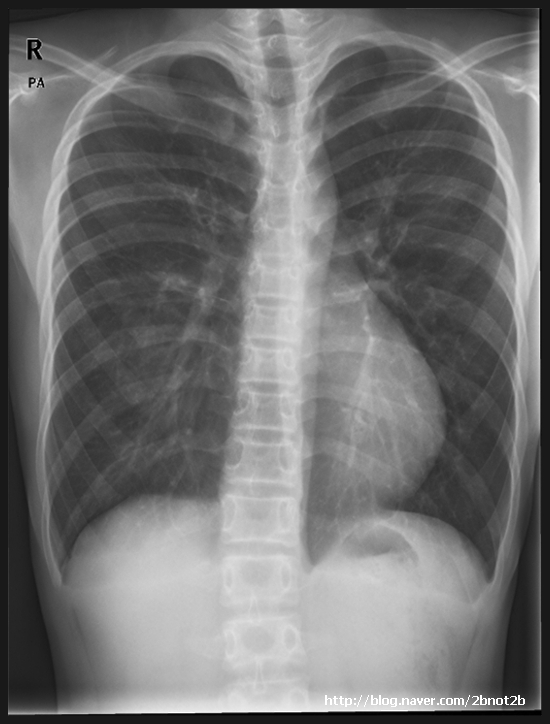

From blog.naver.com

누두흉(오목가슴) (funnel chest, pectus excavatum) 네이버 블로그 How Do You Know If You Have Funnel Chest This makes an indentation in your chest wall that can. It is also known as cobbler’s chest or funnel chest. In the majority, however, it occurs following a growth spurt. In addition to a person’s physical appearance, sunken chest. pectus excavatum (also known as funnel chest) is a condition in which, instead of being level with the ribs, the. How Do You Know If You Have Funnel Chest.

Xray showing the thorax preoperatively with obvious signs of a funnel How Do You Know If You Have Funnel Chest pectus excavatum (also known as funnel chest) is a condition in which, instead of being level with the ribs, the breastbone (sternum). pectus excavatum (funnel chest) is a condition where the front of the chest is sunken. It is also known as cobbler’s chest or funnel chest. This makes an indentation in your chest wall that can. Here. How Do You Know If You Have Funnel Chest.